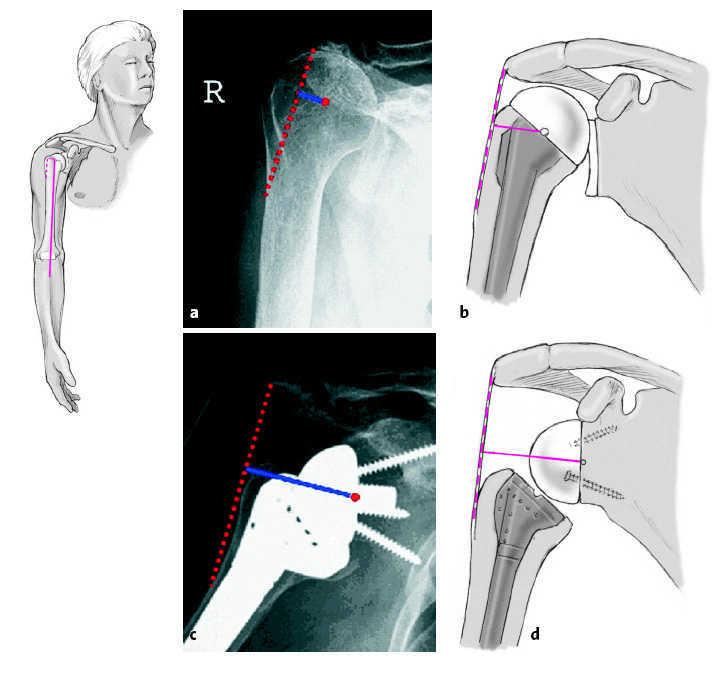

WebLa prótesis invertida de hombro es una opción de tratamiento cada vez más frecuente, cuando hay déficit del manguito de los rotadores. También está indicada en fracturas de. WebPrótesis invertida de hombro ¿En qué consiste? Es un tipo especial de prótesis en la que se invierte la anatomía normal de la articulación de manera que la parte esférica se coloca. WebRecuperación de una prótesis total de hombro invertida Tendrá terapia física ambulatoria para fortalecer el hombro y mejorar la flexibilidad. Debería poder.

Prótesis Invertida De Hombro Rehabilitación. Prótesis Invertida De Hombro Rehabilitación, , , , , , , 0, herenciageneticayenfermedad: La artroscopia resuelve las, herenciageneticayenfermedad.blogspot.com, 614 x 823, jpeg, WebPrótesis Invertida de Hombro Consejos y Rehabilitación Postoperatoria en 4 Fases FASE 1: 1ª a 3ª semanas. Movilización exclusivamente pasiva con elevación (hasta 60º). WebPrótesis invertida de hombro Se emplean en pacientes con daños irreparables en el manguito de los rotadores (tanto en fracturas como en casos de artrosis). El., 20, protesis-invertida-de-hombro-rehabilitacion, Información Interesante